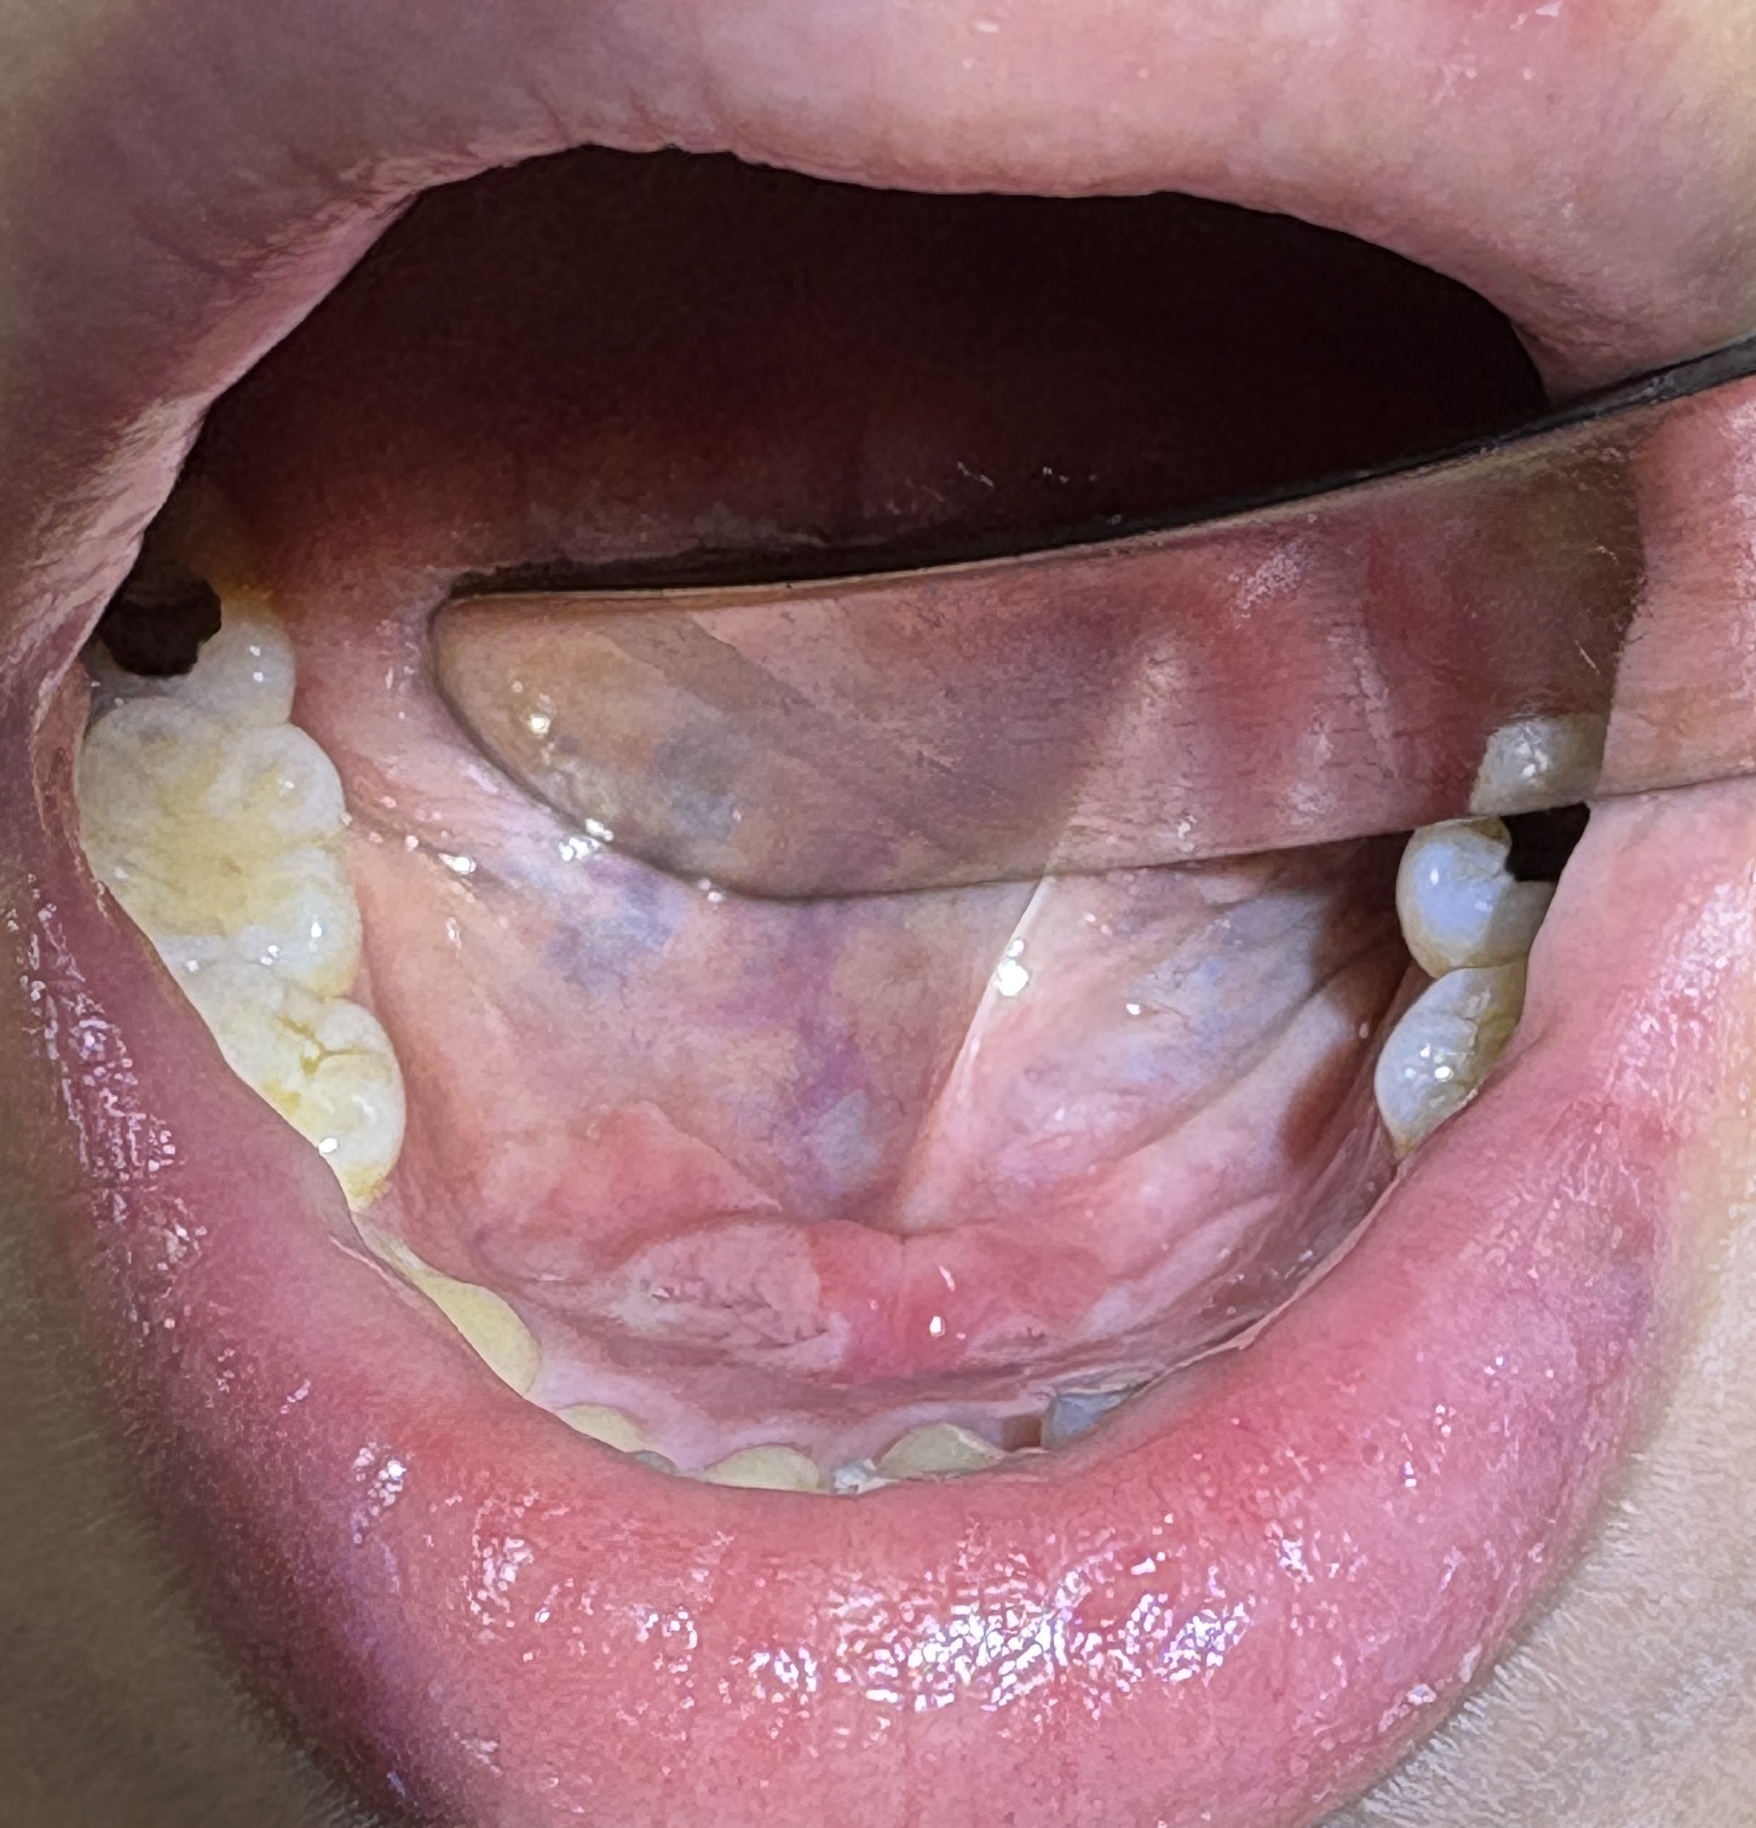

続いて喉👄をチェックします。

ぱっと見 口の中も問題無さそうですが、こういった場合は関連痛を考慮し、舌の裏側や舌の付け根 など 隅々まで

チェックします。

原因が判明しました![]()

どれかと言いますと↓

舌の裏面(医学的には口腔底)に口内炎が出来ていました。 これが痛みの原因です。